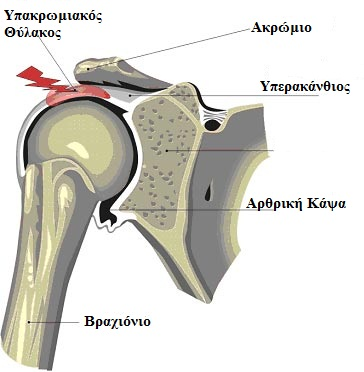

- Θυλακίτιδα

Αυτή είναι μια κατάσταση που μπορεί να προκαλέσει πόνο ή πρήξιμο δίπλα σε μια άρθρωση.

Ο θύλακος είναι ένας μικρός σάκος γεμάτος υγρό που κάθεται κοντά σε ένα οστό. Μαλακώνει και προστατεύει τους κοντινούς ιστούς όταν τρίβονται ή γλιστρούν πάνω από τα οστά.

Θυλακίτιδα είναι η κατάσταση στην οποία ένας θύλακος ερεθίζεται και διογκώνεται. - Παγωμένος ώμος

Η περιστροφική μανσέτα αποτελείται από 4 μύες του ώμου και τους τένοντες τους.Οι τένοντες είναι ισχυρές ζώνες ιστού που συνδέουν τους μύες με τα οστά.Οι τραυματισμοί του στροφικού πετάλου καθώς και οι εναποθέσεις ασβεστώσεων στην περιοχή προκαλούν πόνο στον ώμο και μερικές φορές στον βραχίονα.

τους.Οι τένοντες είναι ισχυρές ζώνες ιστού που συνδέουν τους μύες με τα οστά.Οι τραυματισμοί του στροφικού πετάλου καθώς και οι εναποθέσεις ασβεστώσεων στην περιοχή προκαλούν πόνο στον ώμο και μερικές φορές στον βραχίονα. - Πρόσκρουση ώμου – Αυτό συμβαίνει όταν ένας μυς, ένας τένοντας ή ο θύλακας συμπιέζεται ανάμεσα στα οστά.